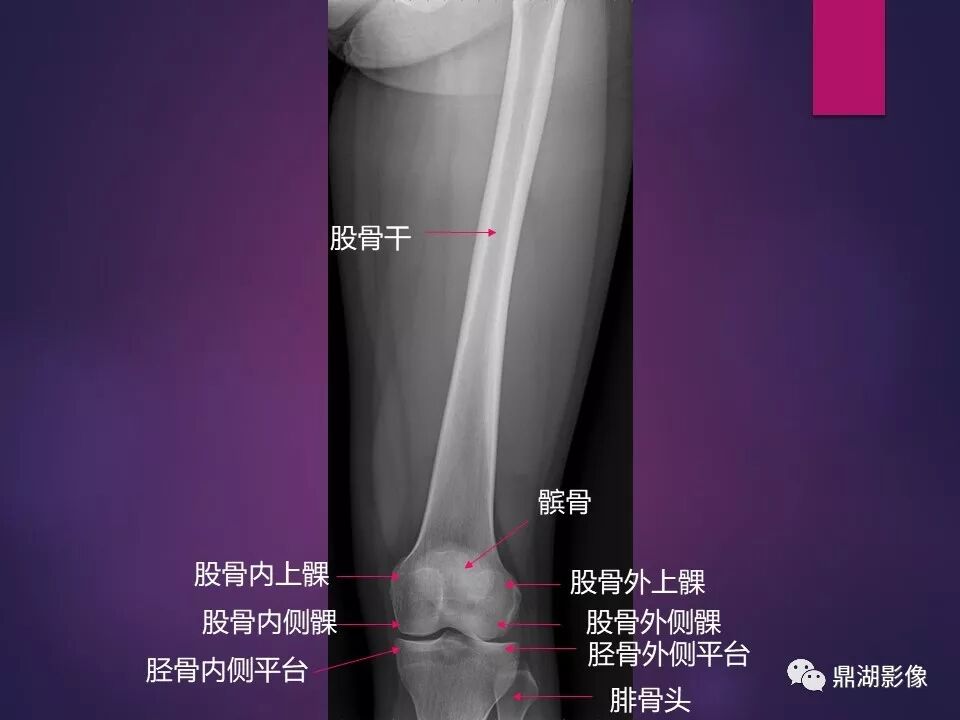

来源于:鼎湖影像 贵阳医学院医学影像系